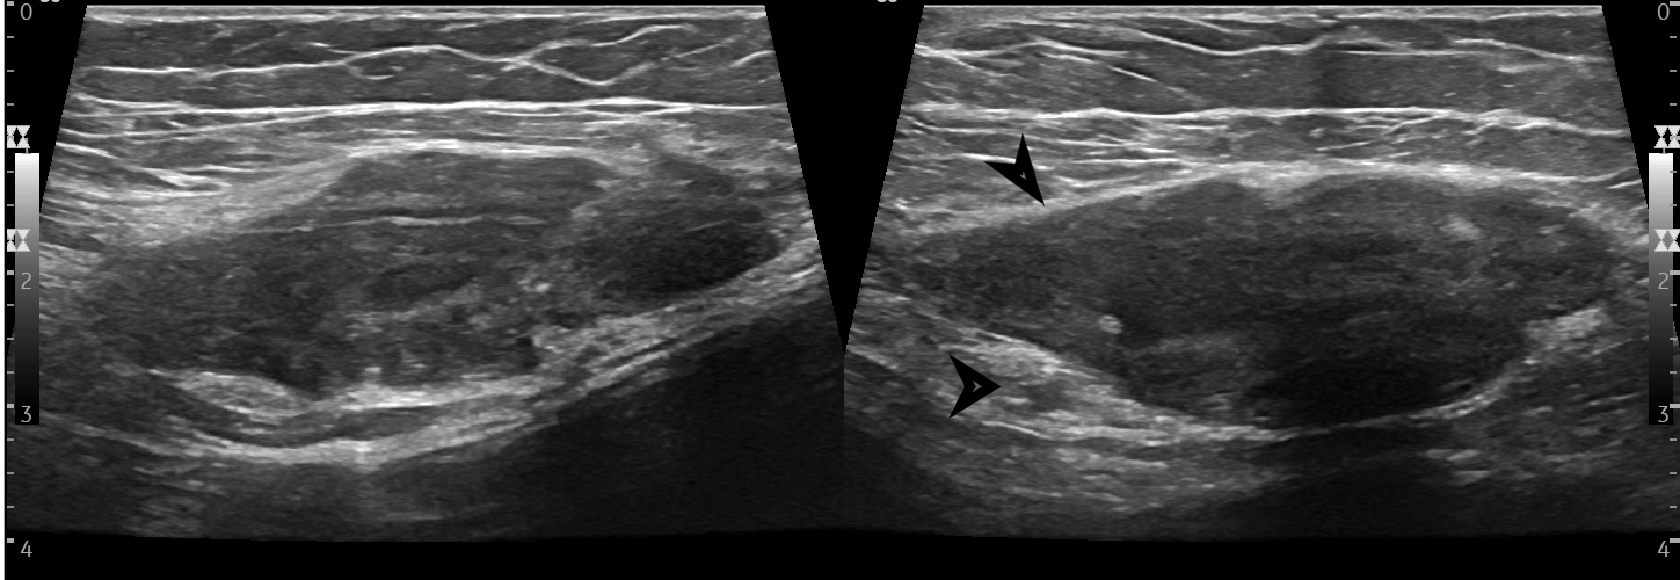

Findings Her entire large bowel was studded with multiple polyps.The rectum and sigmoid had larger polyps as compared to the smaller rest of the bowel which has numerous smaller lesions(Image 1).An ultrasound of her breast was undertaken for the right breasy mass lesion .The ultrasound showed a rather circumscribed lesion in the upper inner quadrant of the right breast splaying fibres of the pectoralis (Black arrowheads in Image 2 ).The lesion was clinically firm to hard and showed no appreciable vascularity on Doppler (Image 3). A USG guided biopsy of the lesion was undertaken which showed spindle cells that were positive for CD99 ,SMA,Desmin and Negative for S100, pan CK, CK 5/6, p63 and CD117,CD 34 . Ki 67 index was less than 3%.(Image 4) . ?eta Catenin showed strong diffuse nuclear positivity(Image 4) . Diagnosis of a spindle cell neoplasm, morphology and immunoprofile favoring Desmoid fibromatosis was given on pathology . Patient eventually underwent prophylactic pancolectomy.She presented a few months post surgery with irregular soft tissue density masses at site of surgical incision on the right rectus (Image 5) and a large intra abdominal mesenteric mass causing distortion and dense bowel adhesions (Image 6). These were diagnosed as fibromatosis on imaging